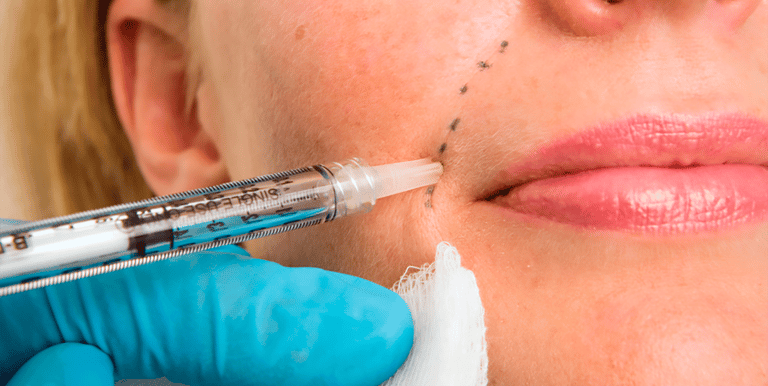

Dermal Filler

Our dermal filler treatments using the RHA collection are designed to restore volume, contour, and structure while adapting to natural facial movement. These fillers are specifically engineered for areas of dynamic expression, making them ideal for subtle facial rejuvenation that looks natural at rest and in motion. This approach focuses on restoring youthful support rather than simply filling lines.